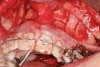

Figure 2b  A corticotomy in SFOT is a surgical technique in which only the cortical bone is cut, perforated, or mechanically altered to the depth of the medullary bone and the medullary bone remains intact.

Figure 2b

Figure 2c  One week postsurgery with mesial buildups on Nos. 5 and 12 and thin pontics on archwire to conceal spaces during closure.

Figure 2c